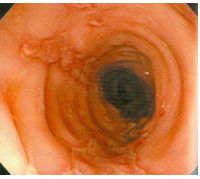

16. 20歲男性,因吞嚥困難接受上消化道內視鏡檢查,報告結果為正常,其食道攝影結果如圖,下列治療方式可緩解其症狀,除了: (A)isosorbide dinitrate (B)atenolol (C)nifedipine (D)endoscopic botulinum toxin injection (E)endoscopic ballon dilatation